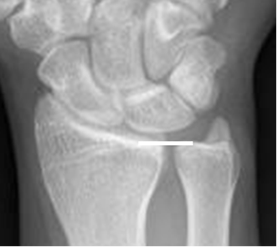

La varianza ulnar es la relación entre los extremos distales del radio y la ulna en la Rx AP. (6). Normalmente se localizan al mismo nivel. (Fig 12).

Fig 12. Varianza ulnar.

Rx AP. Hallazgo normal, con superficie de los huesos al mismo nivel.